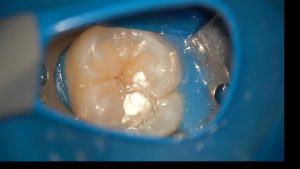

神経を残す治療の中核となるのが、VPT(Vital Pulp Therapy:生活歯髄療法)です。VPTとは、虫歯が神経の近くまで進んでいても、感染部分だけを慎重に取り除き、残せる健康な神経を保護・維持する治療法のことを指します。

この治療では、マイクロスコープ(歯科用顕微鏡)を使って虫歯を精密に除去し、神経の上にMTAセメントを使用して密閉・保護します。MTAについて詳しくはこちらをご覧ください。